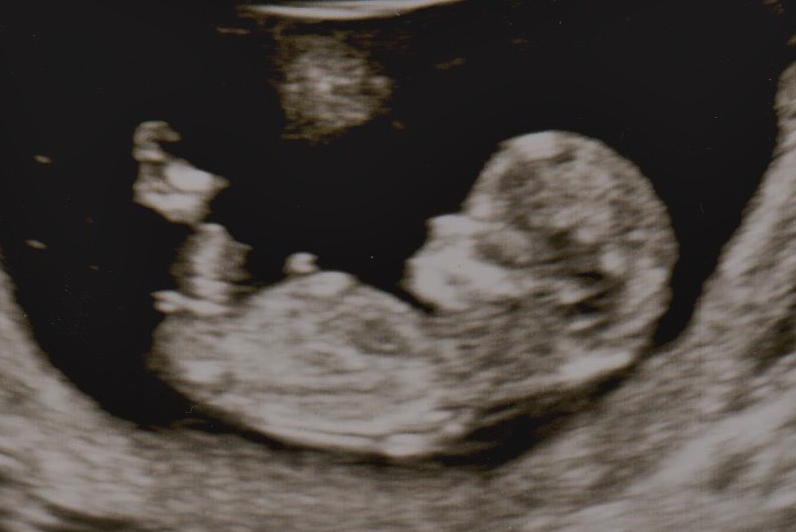

12 weeks. BOY OR GIRL?

Attachment 24329

Still early but going to lean boy on the shape :)